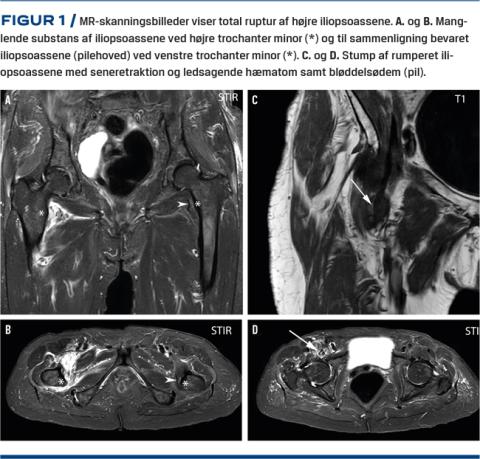

Ved en konventionel røntgenoptagelse kunne der ikke påvises fraktur i højre hofte, bækken eller lårben. En CT viste degenerative forandringer og ledmus i højre hofteled. På mistanke om okkult fraktur eller atypisk femurfraktur blev der foretaget en MR-skanning. Denne viste en komplet afrivning af højre iliopsoassene fra tilhæftningen på trochanter minor (uden ossøs avulsion). Der var ledsagende ødem og hæmatom i det omkringliggende væv (Figur 1).